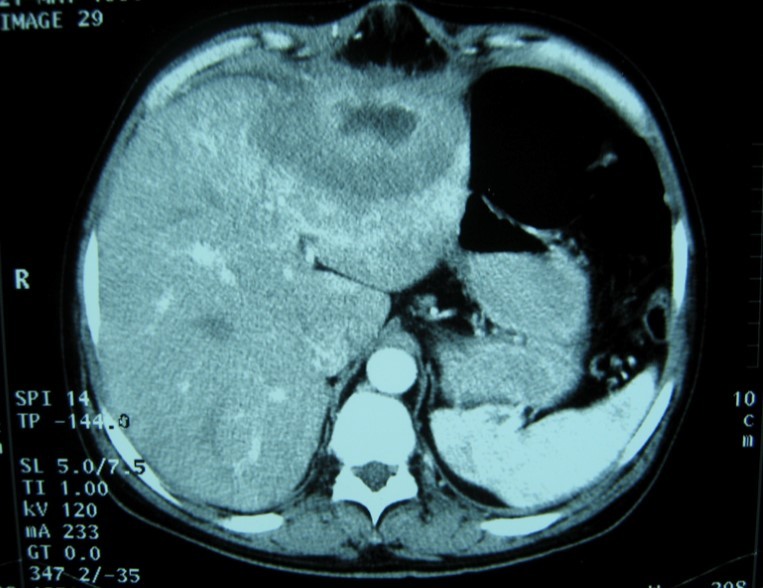

Laboratory analysis showed hemoglobin, 10.9 g/dL; white blood cell count, 9,800 cells/mm3, serum albumin, serum total bilirubin, alanine aminotransferase, aspartate aminotransferase, prothrombin time, hepatitis B surface antigen, and antibodies to hepatitis C, serum alpha-fetoprotein (AFP), carcinoembryonic antigen and carbohydrate antigen 19-9 (CA 19-9) were within normal range. Blood cultures were negative. Chest x-ray was normal. Ultrasound of abdomen showed a 10 cm hypoechogenic lesion in left liver (Figure 1). An abdominal CT showed a well-defined heterogeneous mass situated in his left hepatic lobe measuring 10 cm × 7 cm (Figure 2, Figure 3). The lesion featured central necrosis, a hyper-dense rim and a mild enrichment from the arterial phase in the CT, The diagnosis of primary hepatic tumor was suspected. An ultrasonography-guided needle biopsy of the liver was scheduled in order to rule out malignancy and to have a complete diagnosis. Cytology demonstrated a tuberculosis granuloma, acid-fast bacilli culture was positive (Figure 4). Anti-tuberculous therapy including isoniazid, rifampin, ethambutol, and pyrazinamide were prescribed. The patient completed the 6-month course of medication with success. The patient’s appetite and body weight were restored to previous levels. One year after the completion of treatment, the patient remained completely asymptomatic with disease free.

Figure 3.Abdominal computed tomography with intravenous contrast showing the lesion with ring enhancement.

Abdominal computed tomography with intravenous contrast showing the lesion with ring enhancement.

Computed tomography (CT) and magnetic resonance imaging (MRI) are helpful in diagnosis.

CT findings of tuberculosis abscesses can show low-density focal lesions with or without ring enhancement on contrast administration. These have also been seen in necrotic tumor such as hepatocellular, inflammatory disease and metastatic carcinoma 12.